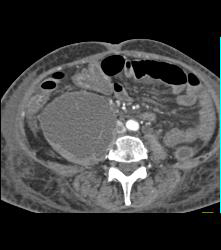

Psoas Abscess and IVC Clot